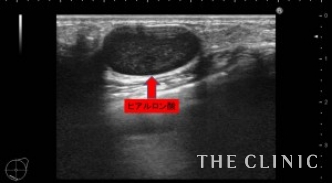

3年前にヒアルロン酸を注入された方です。ヒアルロン酸がしこりになってしまい、見た目・感触ともに無数のしこりが確認出来る状態です。画像は、皮下・乳腺組織内に注入されてしこりになったヒアルロン酸です。

ヒアルロン酸溶解注射を注入して、吸引除去します。

ヒアルロン酸注入によるしこりのエコー診断カルテ